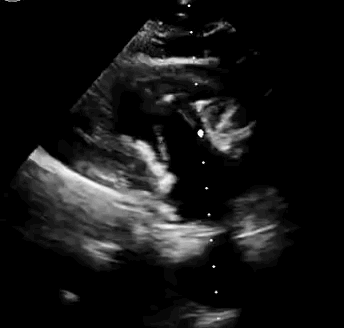

上海中山醫(yī)院葛均波院士、錢菊英院長、周達新教授、潘文志教授、潘翠珍教授、李偉教授共同完成此次臨床前研究。術(shù)后葛均波院士對Lux-Valve Plus的器械操作性能給予了高度評價,DSA和超聲影像也顯示出在本次研究中Lux-Valve Plus的安全性和有效性俱佳。

本次臨床前研究經(jīng)右側(cè)頸靜脈置入LuX-Valve Plus輸送系統(tǒng)可調(diào)彎鞘管,在DSA及超聲引導(dǎo)下將人工三尖瓣瓣膜植入到原有三尖瓣位置,利用獨特的錨定技術(shù)將人工瓣膜支架可靠固定在預(yù)定的位置。